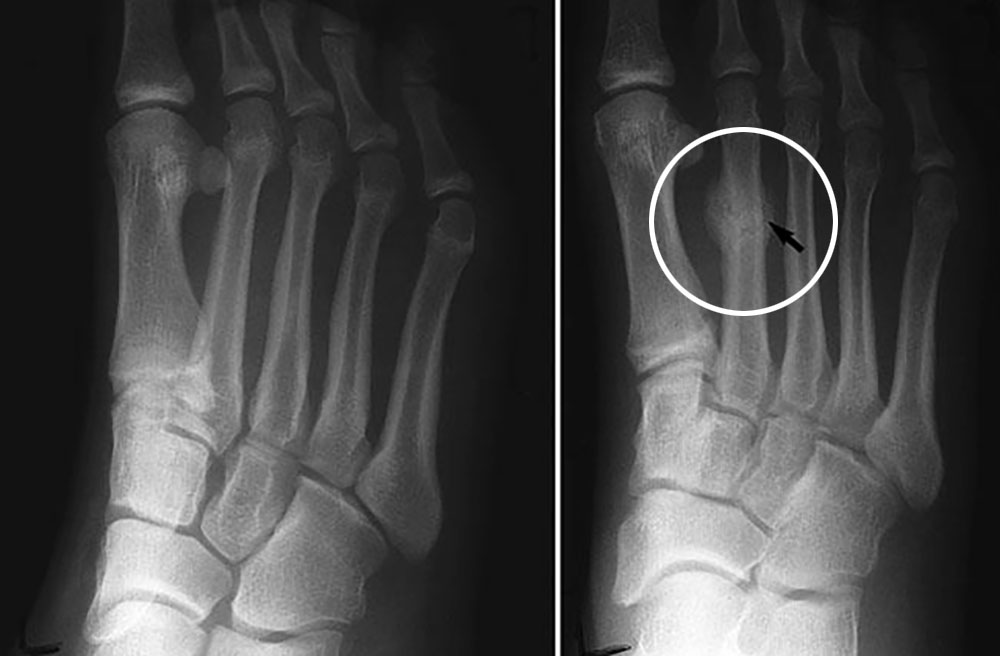

画像引用元:疲労骨折について | みどり整骨院

しかし、疲労骨折と診断されるケースの多くでは、レントゲンに骨折やヒビは写っていません。

患部付近に白くぼやけた影が見えることがありますが、これはカルシウム質が写っているだけで、骨折ではありません。